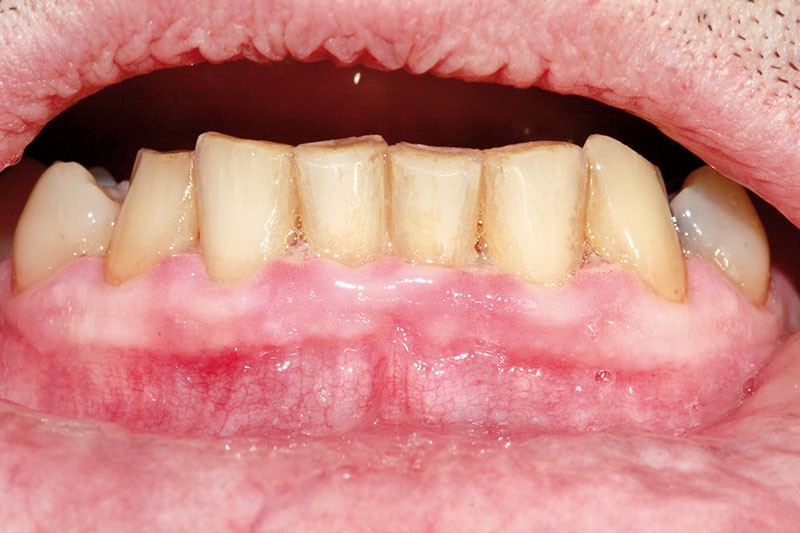

• en endo-buccal, la présence d’une inflammation gingivale sévère notamment au niveau des secteurs antérieurs, caractérisée par des papilles ulcéronécrotiques et hémorragiques au contact, associée à une adénopathie sous mandibulaire droite douloureuse à la palpation.